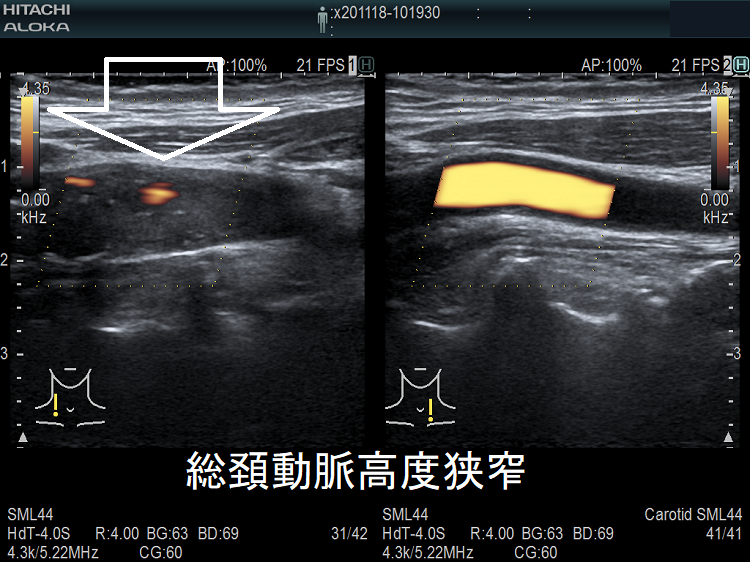

動脈硬化が進んだ血管にはプラーク(コレステロールエステルを大量に含んだ脂質の塊)(矢印)ができて、血管内が狭くなります。血管エコーでプラークを探す。動脈硬化した血管は硬くもろいため、大動脈では血圧に負けて大動脈瘤になることがあります(急性大動脈解離・大動脈瘤)。

甲状腺機能低下症/潜在性甲状腺機能低下症/橋本病、糖尿病などでは動脈硬化が進み(甲状腺と動脈硬化)、頚動脈プラークを形成。頚動脈プラークに血栓ができると、脳へ流れ込んで脳梗塞を引き起こします。最悪、頚動脈そのものが閉塞する事もあります。

脳卒中治療ガイドライン 2021〔改訂2025〕では、軽度~中等度の頸動脈狭窄に頸動脈ステント留置や手術によるプラーク除去(頸動脈内膜剥離術)を行わないよう勧めています。

高度狭窄か脳梗塞を伴う中等度以上狭窄に対し、頸動脈ステント留置よりも手術によるプラーク除去(頸動脈内膜剥離術:CEA)を推奨しています。手術不能例には頸動脈ステント留置(CAS)。